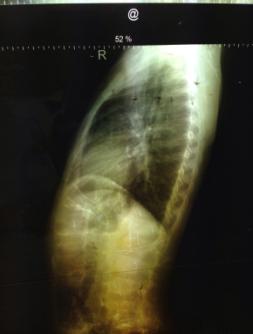

Пациент

Т.Е., 9 лет, рентген в прямой и боковой проекциях